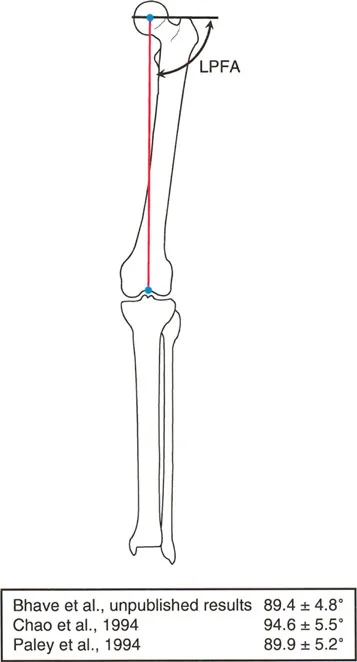

الزاوية الفخذية القريبة الوحشية (LPFA)

وصف بالي وزملاؤه طريقة موثوقة لتحديد توجيه الورك: خط يمتد من طرف المدور الكبير (بروز عظمي في أعلى الفخذ) إلى مركز رأس عظم الفخذ.

* الزاوية المتكونة بين هذا الخط والمحور الميكانيكي لعظم الفخذ هي LPFA.

* القيمة الطبيعية المقبولة لـ LPFA هي 89.9 درجة ± 5.2 درجة (وغالباً ما تبسط إلى 90 درجة في الممارسة السريرية).